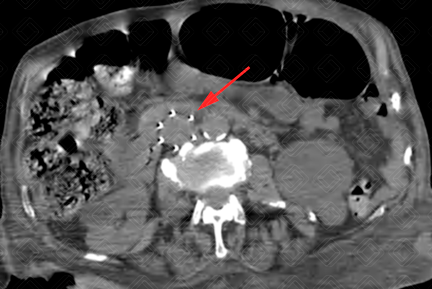

Texto alternativo para a imagem Créditos: Dra. Elazir Mota - Rio de Janeiro/RJ

Descrição das imagens: Tomografia computadorizada do abdome. Filtro metálico na veia cava inferior, de localização infrarrenal (setas vermelhas).